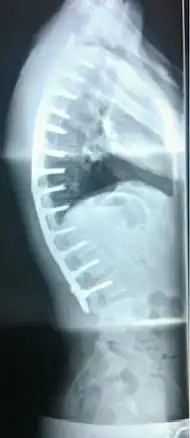

Scheuermann's disease

Other names | Scheuermann's kyphosis, Calvé disease, idiopathic juvenile kyphosis of the spine |

Scheuermann's disease on lateral Xray of the T spine | |

In severe or extreme cases, patients may be treated through an extensive surgical procedure in an effort to prevent the disease from worsening or harming the body. The skeletal deformity caused by Scheuermann's disease can be corrected or partially corrected with surgical procedures, almost all of which include multi-level spinal fusion and hardware instrumentation, i.e., rods, pedicle screws, etc. It is important to realize the surgery aims to reduce pain, and not cosmetic defect. As always, surgical intervention should be used as a last resort once conservative treatment fails or the patient's health is in imminent danger as any surgical procedure is not without risk. However, the chances of complication are relatively low, and the surgeries are often successful.

There are two primary surgical techniques to correct kyphosis: posterior-only fusion and anterior/posterior fusion. While debate lingers over which surgical approach is optimal, several studies published since 2018 suggest treatment trends are favoring posterior-only fusion.[17][18][19]

The classic surgical procedure entails entering two titanium rods, each roughly 1.5 feet (0.46 m) long (depending on the size of the kyphosis) into the back on either side of the spine. Eight titanium screws and hardware are drilled through the bone to secure the rods onto either side of the spine. On the internal-facing side of the spine, ligaments (which can be too short, pulling the spine into its abnormal shape) must be surgically cut or released, not only stopping part of the cause of the kyphosis, but also allowing the titanium rods to pull the spine into a more natural position. The damaged discs between the troubled vertebrae (wedged vertebrae) are normally removed and replaced with bone grafting from the hip or other parts of the vertebrae, which once healed or "fused" will solidify. The titanium instrumentation holds everything in place during healing. The patient can expect to remain in hospital for a minimum of a week, and possibly longer. They may then be required to wear a brace for several months more to ensure the spine heals appropriately. The titanium instrumentation may stay in the body permanently, or be removed years later. Patients who have undergone such surgery may need physical therapy to manage pain and mobility. Recovery can be prolonged: typically patients are not allowed to lift anything above 5–10 pounds (2.3–4.5 kg) for 6 months to 1 year, and many are out of work for 3 to 6 months. However, once the fusion is solidified, most patients can return to their usual lifestyle within 1–2 years.